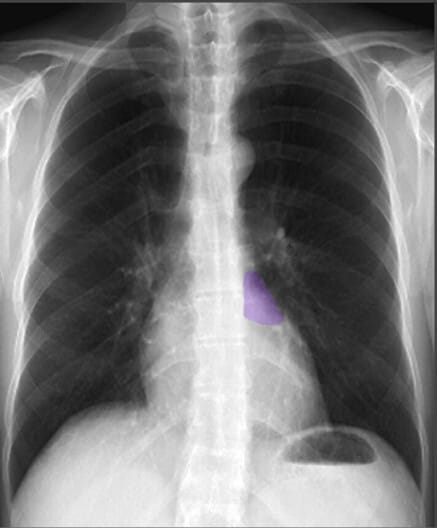

Landmarks in Chest X-ray (PA view)

폐와 심장 및 흉곽 구조물을 분석할 때 유용한 해부학적 지표로는 유방 음영(breast shadows), 심장 크기(cardio-thoracic ratio), 늑골횡격막각(costophrenic angles), 위 기포(gastric bubble) 등이 있습니다.

| 심장 크기 (Cardiac Width) |

| ✅ 정상적인 심장 크기는 흉곽 폭의 50% 이내여야 하며, 이를 심흉비(cardiothoracic ratio, CTR)라고 합니다. 비정상적으로 증가하면 심부전 또는 심장 비대의 가능성을 고려해야 합니다. |

| 위 기포 (Gastric Bubble) |

| ✅ 좌측 횡격막 아래에서 나타나는 공기음영으로, 정상적인 해부학적 지표 중 하나입니다. 위치가 변하면 장폐색 등 복부 문제를 의심할 수 있습니다. |